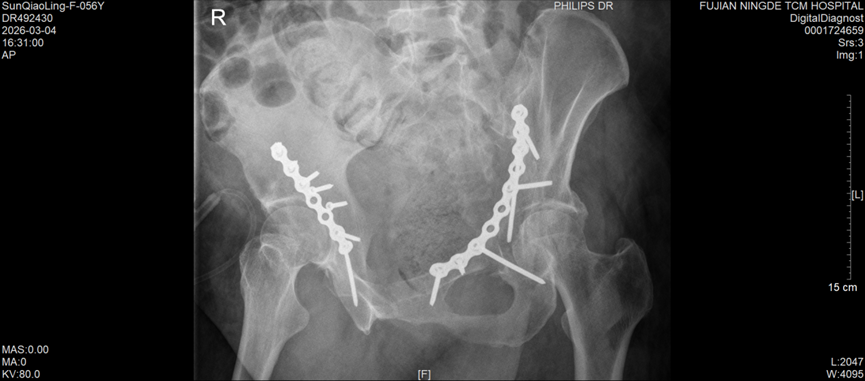

手术过程中,创伤骨科团队凭借扎实的解剖知识和娴熟的手术操作技巧,小心翼翼地进行组织精细分离,精准完成骨折复位,随后顺利实施牢靠的内固定操作,全程注重保护周围神经血管,严格控制术中出血和组织损伤。得益于周密的术前方案和精准的术中操作,此次手术总出血量控制在传统单侧髋臼骨折手术的常规水平,手术进展顺利。

术后,医护团队针对孙女士的具体情况,实施个体化镇痛、抗凝治疗,并引入快速康复(ERAS)管理理念,全程密切监测患者病情变化,及时调整康复方案。目前,孙女士恢复情况良好,未出现任何术后并发症,髋关节功能正稳步恢复,已进入有序的康复阶段。